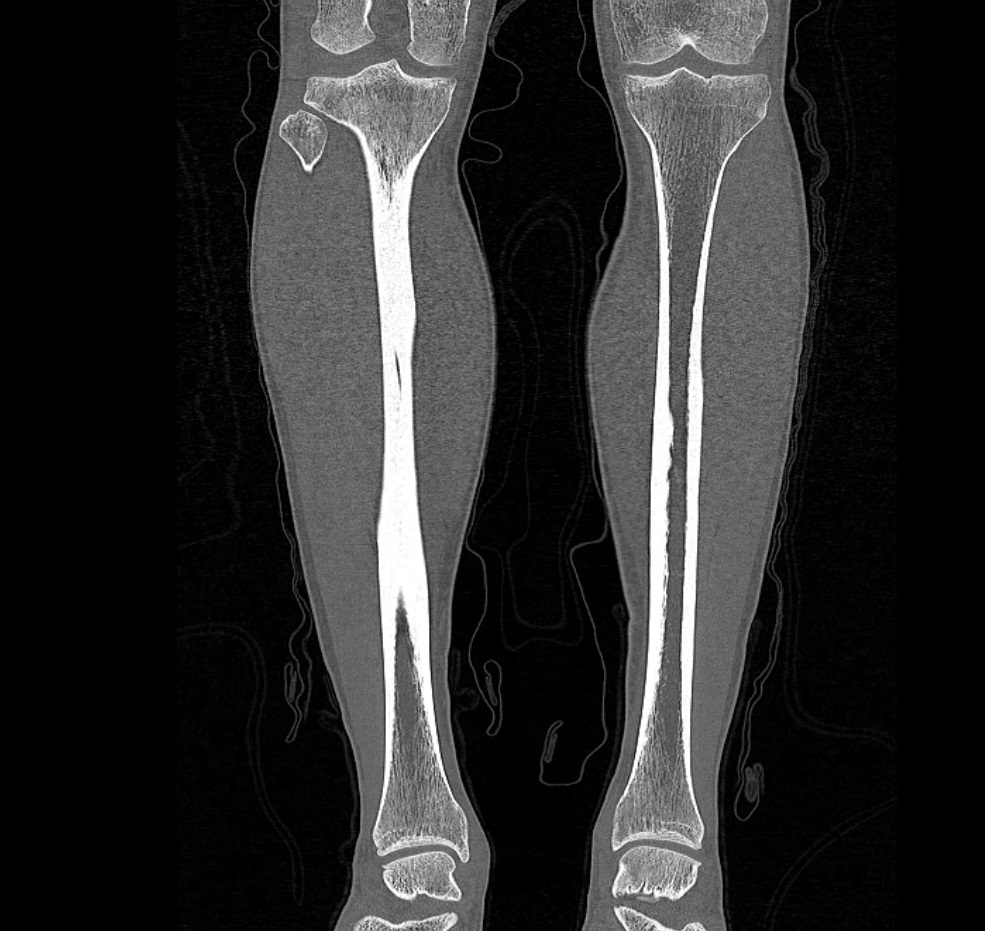

Наиболее информативным методом исследования костных структур и мягких тканей голени является мультиспиральная компьютерная томография. КТ относится к лучевым методам исследования и основана на применении ионизирующего излучения и последующей цифровой обработке данных, полученных при КТ-сканировании.

В наших медицинских центрах обследование области голени проводится на современных мультиспиральных компьютерных томографах последнего поколения TOSHIBA AQUILION. При помощи рентгеновских лучей аппараты послойно сканируют исследуемую область с толщиной среза от 0,5 мм. В результате получаются детальные снимки и цифровые трехмерные изображения в мельчайших подробностях. При этом пациент получает уменьшенную дозу рентгеновского облучения.

Мультиспиральная компьютерная томография позволяет оценить структуру костей голени, выявить переломы, воспалительные изменения, участки деструкции костной ткани, диагностировать опухолевые образования.